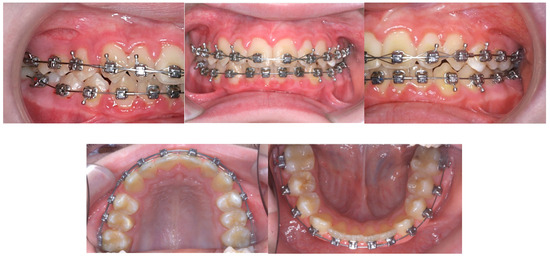

A 0.022 X 0.028-in DamonQ® (Ormco, Glendora, CA, USA) passive self-ligating pre-adjusted edgewise appliance was used (Figure 3). The maxillary arch was bonded to allow initial alignment, and the bonding of the mandibular arch was completed one month later. Upper incisors and canines were bonded with high torque brackets, and lower incisors and canines were bonded with low torque brackets. This was due to the requirement of employing Class II mechanics, which was expected to result in retroclination of the upper incisors and proclination of the lower incisors. As a result, placing high-torque brackets on the upper incisors and low-torque brackets on the lower incisors would help counteract these adverse effects [34,35]. Brackets were positioned more incisally in the upper anteriors to allow for relative intrusion.

Figure 3.

Progress intra-oral photographs.

Initially, a 0.014-inch copper nickel–titanium (CuNiTi) archwire was used in the upper arch, and a 0.018-inch CuNiTi archwire was used in the lower arch to level and align the teeth. When the lower arch was bonded, bracket interferences required the placement of two bite turbos made from glass ionomer cement on the lower first molars. The maxillary archwire was changed to a 0.018-inch CuNiTi, and two composite bite turbos were applied to the palatal surfaces of the maxillary central incisors at month three. Early light short elastics (3/16″, 2 oz) were used from the upper first premolars to the lower first molars to protract the mandible and extrude the lower molars. Posterior bite turbos were removed as soon as the lower arch was aligned, at month five. At 11 months, upper and lower 0.014 X 0.025-inch CuNiTi archwires (Ormco, Glendora, CA, USA) were placed, followed by a 0.016 X 0.025-inch CuNiTi archwire. The light short elastics were replaced with conventional Class II elastics (¼″, 3.5 oz) from the upper canines to the lower first molars. A 0.018 X 0.025-inch CuNiTi archwire was subsequently used at month thirteen, and the upper anterior teeth were consolidated with a figure of eight steel ligature tie. The 0.019 X 0.025-inch stainless steel (SS) archwires were placed as the working archwires in both the upper and lower arches fifteen months after starting treatment. Fixed upper and lower lingual bonded retainers were placed at the end of active treatment, as the patient was approaching his fifteenth birthday.